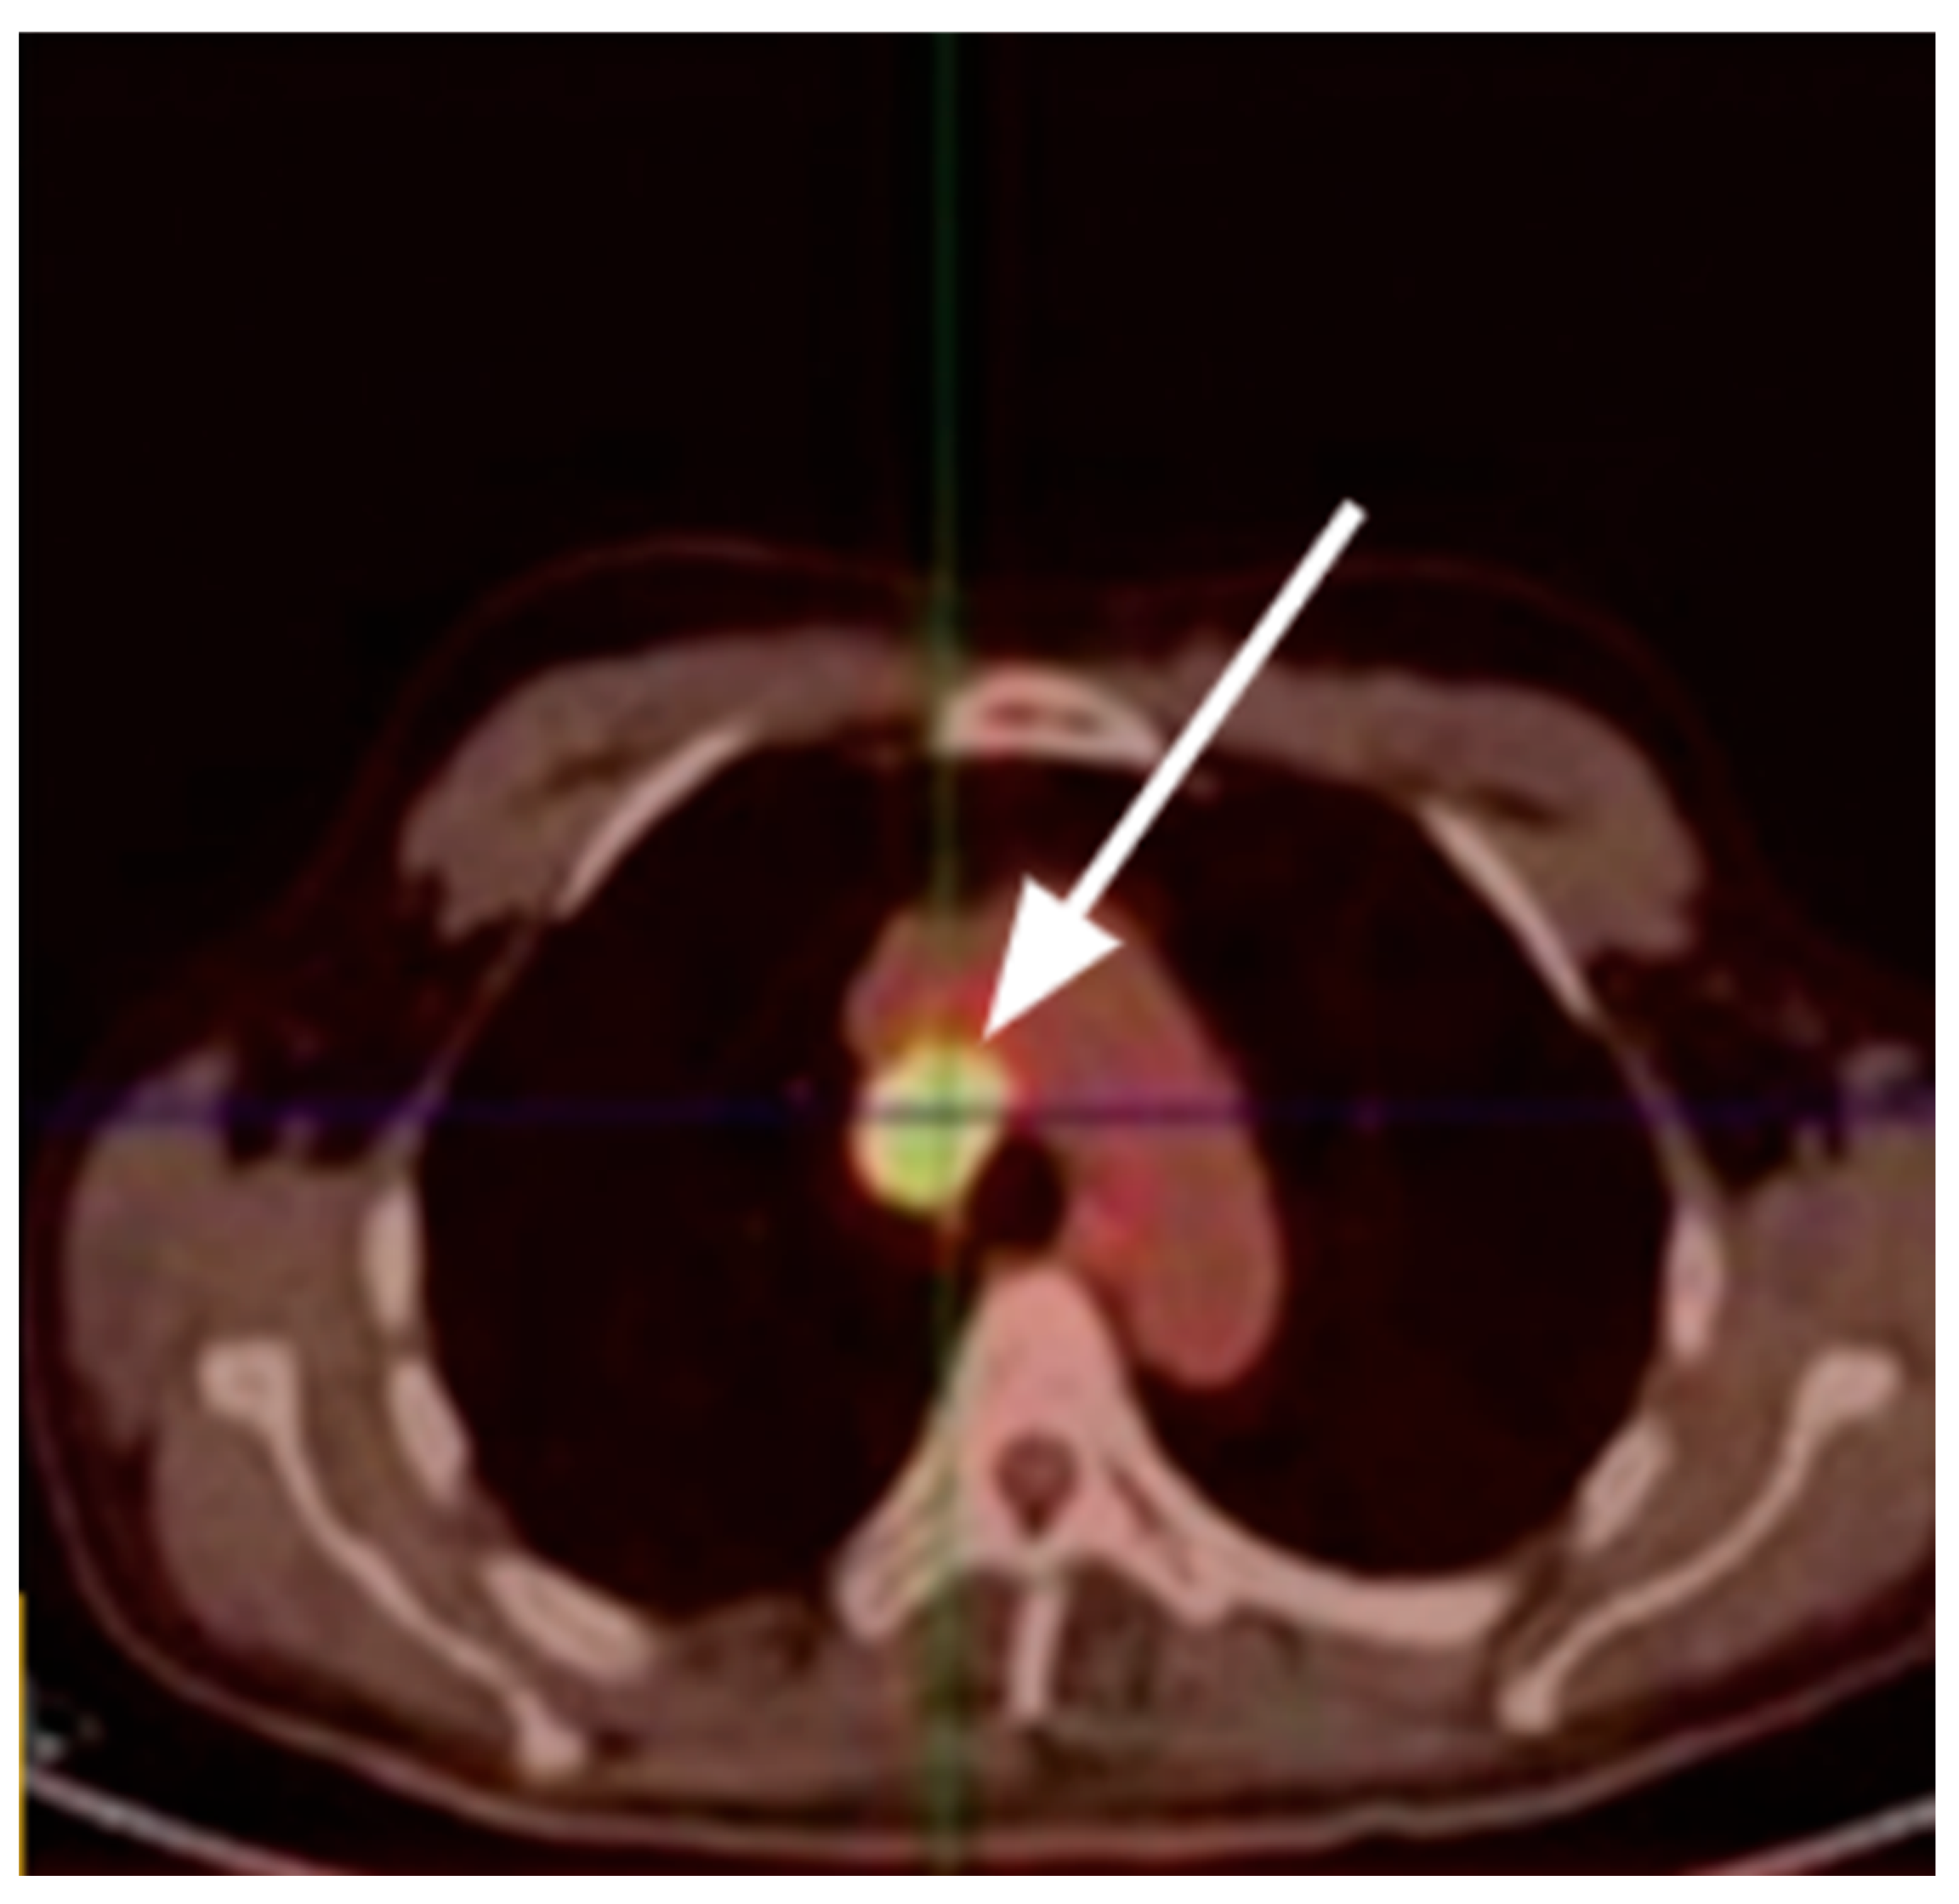

- Treglia, G.; Giovanella, L.; Lococo, F.; Bertagna, F. An Unusual Case of Thymic Carcinoid Causing Cushing’s Syndrome Due to Ectopic ACTH Secretion Detected by (18)F-FDG PET/CT. Rev. Esp. Med. Nucl. Imagen Mol. 2014, 33, 253–254. [Google Scholar] [PubMed]

- Isidori, A.M.; Sbardella, E.; Zatelli, M.C.; Boschetti, M.; Vitale, G.; Colao, A.; Pivonello, R. ABC Study Group Conventional and Nuclear Medicine Imaging in Ectopic Cushing’s Syndrome: A Systematic Review. J. Clin. Endocrinol. Metab. 2015, 100, 3231–3244. [Google Scholar] [CrossRef] [PubMed]

- Zisser, L.; Kulterer, O.C.; Itariu, B.; Fueger, B.; Weber, M.; Mazal, P.; Vraka, C.; Pichler, V.; Kautzky-Willer, A.; Hacker, M.; et al. Diagnostic Role of PET/CT Tracers in the Detection and Localization of Tumours Responsible for Ectopic Cushing’s Syndrome. Anticancer. Res. 2021, 41, 2477–2484. [Google Scholar] [CrossRef]